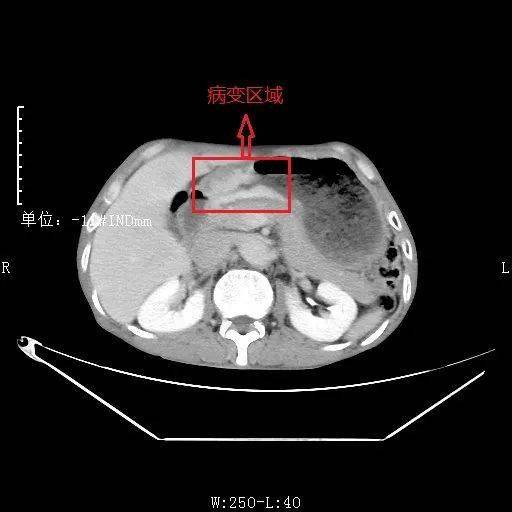

ct诊断误区胃窦壁增厚的诊断难点及误区这几点千万注意

胃壁增厚疾病ctmri影像表现

胃壁增厚性病变的ct表现ppt